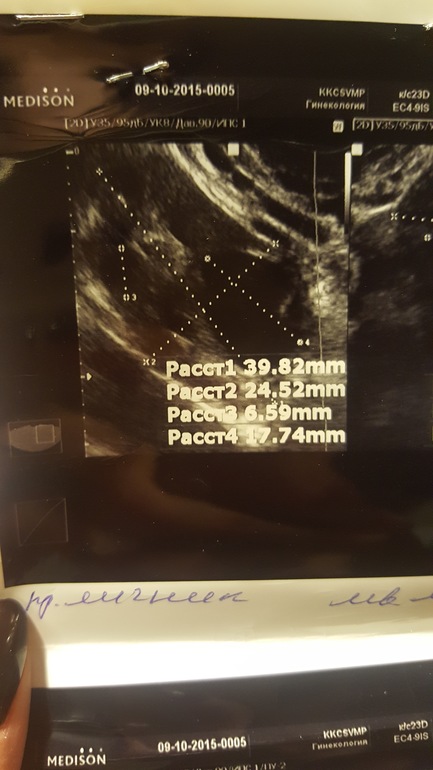

Добрый день,девочки.Дано:35ДЦ,задержка уже ну как минимум 3-5 дней...Тесты отрицательные ,на 23 ДЦ нашли в эндике включение 0,34 мм.Овуляцию чувствовала на 15-17 дц (точно не помню но не раньше ,не позже)резкая боль в ЛЯ,чуть розово-красных выд-ий.Сегодня УЗИ :Эндик 7мм(однородный)в ПЯ ЖТ 13мм??На 90%ЖТ как сказал врач.А мне вот не кажется,что это похоже на ЖТ,но я не врач,хз.В ЛЯ только фоллики..И никакого образования в Эндик нету(специально не сказала ,что там что-то находили,для чистоты эксперимента)Но когда будут М не сказали,ЖТ или нет не понятно.Да и чувствовала я 💯 процентов слева!!!Прилагаю фото,где два снимка -это сегодня ПЯ и ЛЯ,где один с точкой это включение -на 23 дц,ну и последний сегодня эндик .Как думаете,ЖТ???

фолик

и из него желтое тело